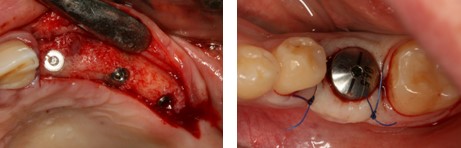

- Chirurginių etapų analizė. Ką būtina atlikti, kad implantai tarnautų ilgai?

- Išsami protezavimo detalių ir instrumentų analizė: kada ką naudoti?

- Išsami protezavimo etapų analizė.

Praktinė dalis:

implantacija į plastikinį žandikaulį; atspaudų ėmimas nuo implantų skirtingomis metodikomis, aptariant kurią metodiką kada rinktis; susipažinimas su implantavimo instrumentais ir detalėmis.